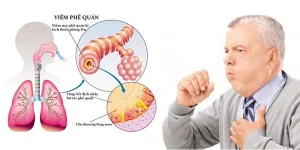

Bệnh nhiễm trùng đường hô hấp: Tổng quan về nguyên nhân, triệu chứng, cách điều trị và phòng ngừa hiệu quả để bảo vệ lá phổi của bạn

Chào bạn, hôm nay chúng ta sẽ cùng nhau tìm hiểu về một nhóm bệnh lý rất phổ biến mà hầu như ai cũng đã từng mắc phải ít nhất một lần trong